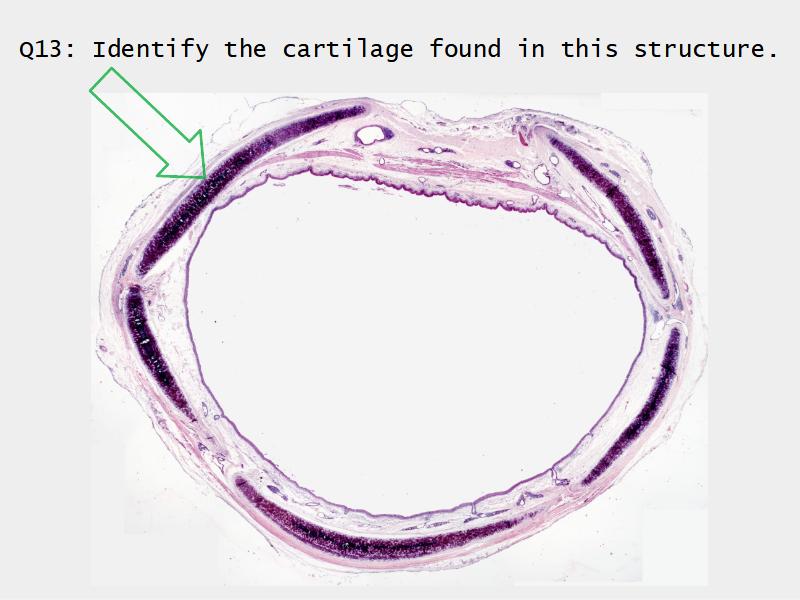

Slides: Respiratory System

- Slide 73: Trachea

Trachea